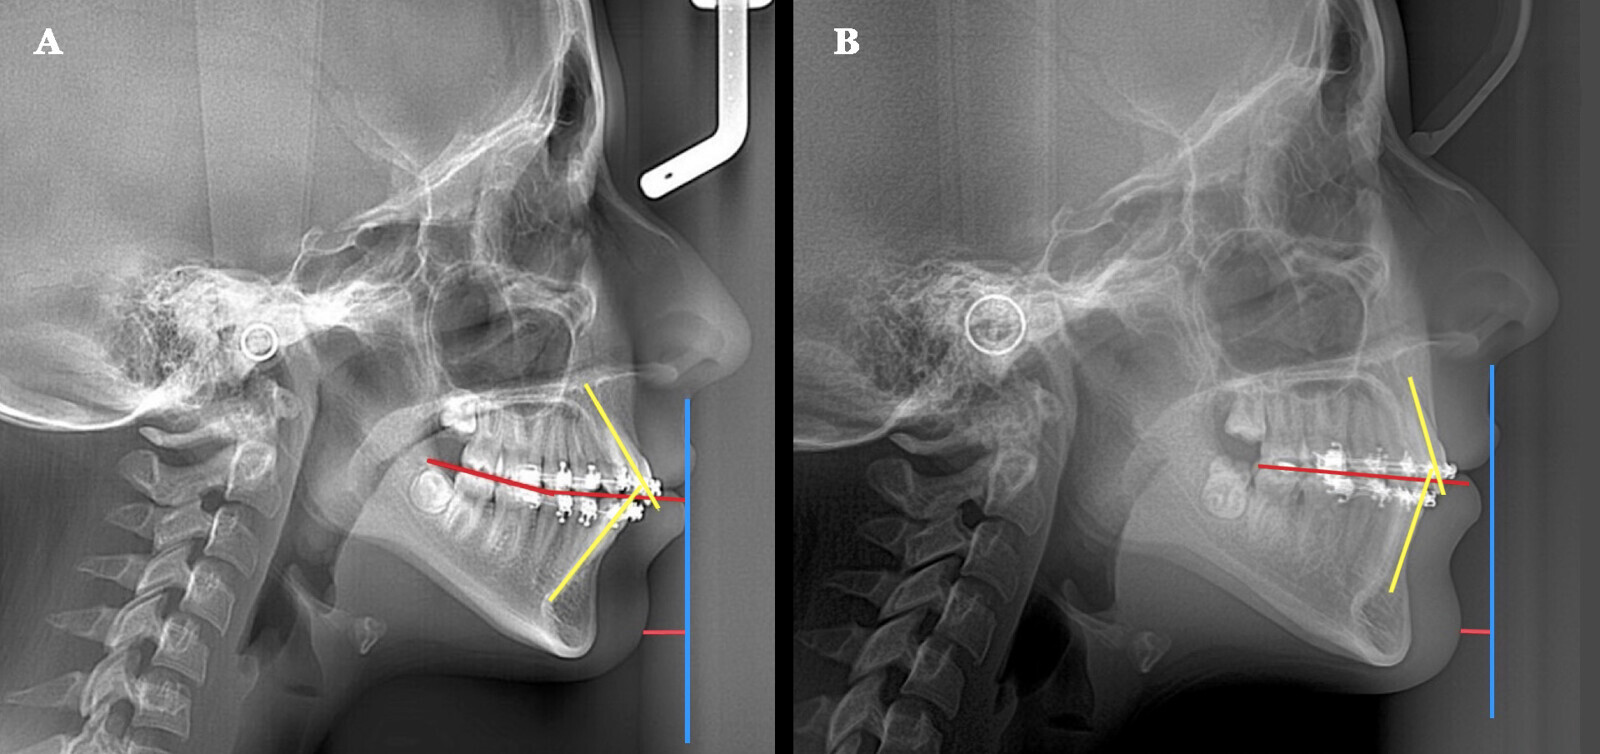

Figura 5. Comparación de un pre y postratamiento de ortodoncia. A) Plano oclusal inclinado. B) Se consiguió la rotación antihoraria del plano oclusal, mejorando a su vez la proyección del mentón.

Este es otro ejemplo en el cual se realizó exodoncia de los primeros bicúspides superiores e inferiores, empleando el protocolo anteriormente descrito para conseguir la rotación antihoraria.